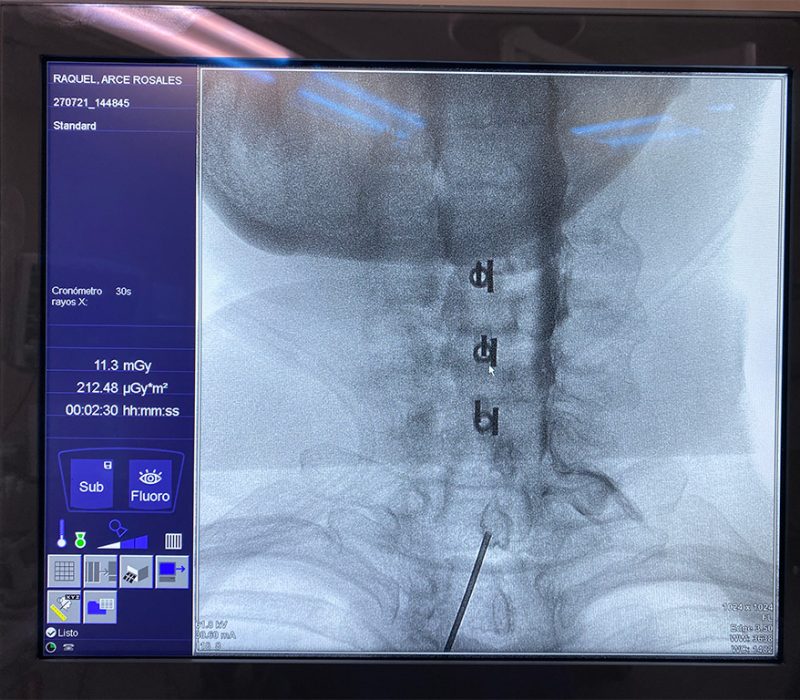

Un bloqueo es una inyección dirigida a un músculo, nervio o articulación de un anestésico local acompañado de un antinflamatorio, se basa en la interrupción de la nocicepción o de la señal dolorosa, en otras palabras se trata de «apagar» el dolor. Puede ser temporal y reversible por lo que en ocasiones le llamamos bloqueos diagnóstico, pues al aislar una estructura dolorosa podemos identificar de forma más específica el origen del dolor y posteriormente ofrecer técnicas con mayor durabilidad.

Estos procedimientos se deben realizar siempre bajo guía fluoroscópica y/o con guia de ultrasonido, esto permite obtener imágenes en tiempo real de las estructuras internas con lo que el procedimiento tiene mayores índices de eficacia al estar seguros que el medicamento esta siendo depositado en la estructura deseada y ofrece mayor seguridad para el paciente.